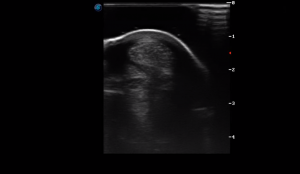

SIMON Ultrasound Database

This ultrasound database is a free resource for students and doctors!

Our collection includes videos of dogs, cats, horses, cows, humans, and many other species!